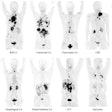

Clinically Meaningful AI Detection of Interval Cancers